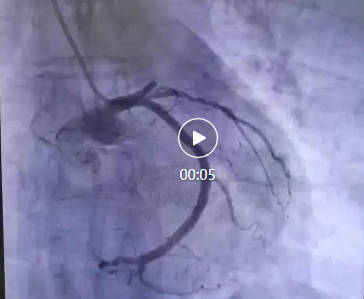

品質(zhì)國(guó)文丨跑贏死神!突發(fā)急性前壁心肌梗死男子成功獲救

2月9日清晨,張先生(化名)突然感到胸口一陣劇烈的壓榨性疼痛,伴隨著冷汗和呼吸困難。他意識(shí)到情況不妙,立即撥打了急救電話。救護(hù)車(chē)迅速將他送往當(dāng)?shù)蒯t(yī)院,經(jīng)過(guò)急診醫(yī)生的初步檢查,診斷為“急性前壁心肌梗死”,病情危急,當(dāng)?shù)蒯t(yī)院不具備治療能力,立即轉(zhuǎn)入我院。! 閱讀量:1008

國(guó)文醫(yī)院心血管內(nèi)科團(tuán)隊(duì)再次為一例復(fù)雜病變患者成功植入了最新型美敦力第四代ResoluteOnyx藥物涂層支架。這是一款只需要一個(gè)月雙聯(lián)抗血小板治療的藥物洗脫支架,具備輸送靈活,清晰顯影,柔順貼合,尺寸矩陣全面,力顯非凡等優(yōu)勢(shì),為冠心病患者提供了新的治療選擇。 閱讀量:1529